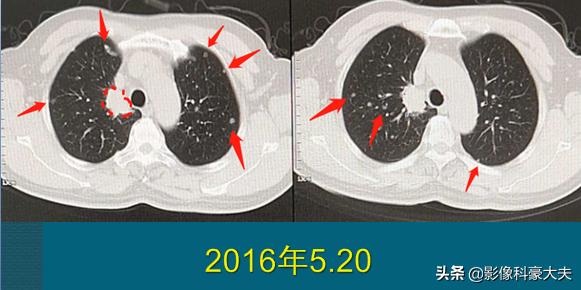

豪大夫不是吹牛,很多晚期肺癌病人都在创造和延续奇迹!今天还有一位复查的病人,3年半前确诊为肺癌晚期,双肺一百多个转移瘤和多发骨转移:

这位病人67岁,男性,因为咳嗽、胸痛做肺部CT,右上肺癌3.1cm,边缘有毛刺。因为肿瘤贴近胸膜,癌细胞沿着胸膜脉管系统(主要是淋巴系统)快速播散,像种子一样在双肺生根发芽,长出100多个转移瘤,还有胸椎、肋骨的多发骨转移,已经无法手术。

后来穿刺证实为低分化肺腺癌,基因检测阳性。他采用靶向治疗为主的综合治疗,吃了两年吉非替尼,定期服用双膦酸盐药物控制骨转移,辅助应用一下调理免疫的药物,从今年开始更换新的靶向药物,目前控制比较理想:

晚期癌症病人的治疗费用不算低,很多时候是用钱续命。有的人有药,买不起;有的人有钱,没有药了(靶向药存在耐药期,长短不一,幸运的人可以5年以上不耐药,不幸的可能只维持几个月就需要换药),这方面还需要更多的研发,找到更多的靶点或者新的方法,让更多的病人有药可用!